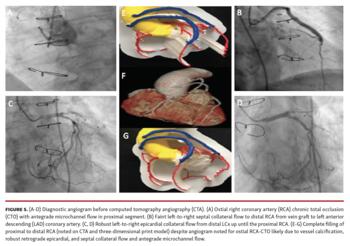

Case 3 (Figure 4 and Figure 5):

a. Patent left main coronary artery (4Aa, 4Bb).

b. Vein graft to mid LAD is widely patent without any significant stenosis and the anastamotic site can be clearly seen at the mid segment of the LAD with patent native distal vessel (4Ab, 4Bd, 4Ca).

c. Vein graft to OM1 is widely patent and the anastamotic site can be clearly seen; native distal OM is patent without significant disease (4Ac, 4Be, 4Ca). The atrioventricular groove/LCx is also seen (4Ac, 4Bb).

d. The native RCA, although chronically occluded at the ostium on diagnostic angiogram (4Ba, 5A), is noted to fill until the distal RCA on 3D-CTA and 3D-PM (4Aa, 4Cb-4Cc, 5E-5G). As seen in case #1, this unexpected finding is likely from native vessel calcification along with robust left-to-right epicardial collaterals from the distal LCx allowing retrograde filling to the proximal RCA (5C-5D), septal collaterals from LAD vein graft (5B), and antegrade proximal vessel microchannel filling (5A).